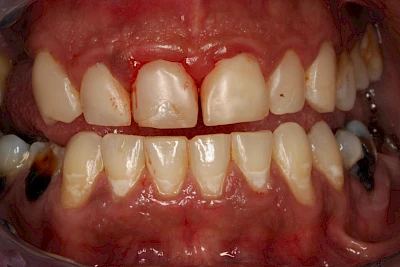

Dunkle bzw. Rötliche Verfärbung

Ist ein einzelner Zahn deutlich dunkler als die Nachbarzähne kann das ein Zeichen sein, dass der Nerv abgestorben ist. Unter Umständen wurde bereits eine Wurzelkanalbehandlung vom Zahnarzt durchgeführt. Eine Abklärung durch den Zahnarzt ist in jedem Fall sinnvoll.